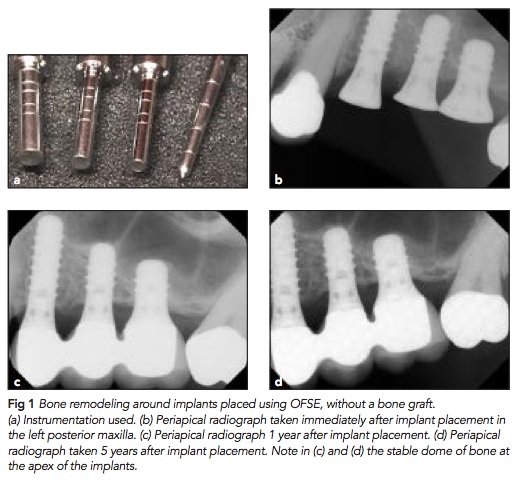

通常我們在上顎後牙區, 有遇到sinus比較低但是還可以接受(還有5mm的bone)的時候, 可以使用osteotome的方式去提高上顎竇. 幾乎在提高的同時, 我們會補一些材料, 但是這個研究的特性是他使用很多的短植體, 然後他不補骨粉.

在541位患者中植入了926隻植體, 5年的存活率是98.3%, 10年的存活率是97%. 其中更有小於5mm骨頭高度的情況, 平均增加的高度是1-5mm. 其中幾點可以注意:1. 增加的高度有65%以上小於3mm, 2. Straumann tissue level的成功率大於Nobel Replace大於其它, 3. Failure implant有6隻在製作假牙前失敗, 另外6隻是之後, 所以會不會失敗其實跟一般植牙成功率差不多.